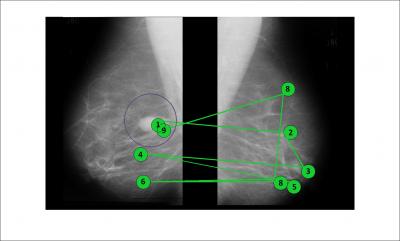

For the study, Grimm and her colleagues used a database of images provided by the Mammographic Image Analysis Society that includes both images and text files that contains coordinates of abnormalities and their size.

"Expert diagnostic radiologists have a particular search pattern that is not the same as that of a novice," Grimm says. "We don't know exactly what they're doing, but they tend to do a fairly broad scan and then fixate on parts of the image that have a tumor-like texture. A novice might instead attend to brighter spots in the image or fail to scan all of it."

Bailey hired an expert radiologist at the Rochester Institute of Technology to view and mark 65 images from the database. The expert's scanpath was recorded during this process by an eye-tracking system.

During the experiment, subtle gaze direction was used to guide a group of novices along the expert scanpath. A control group viewed the mammograms without gaze manipulation.